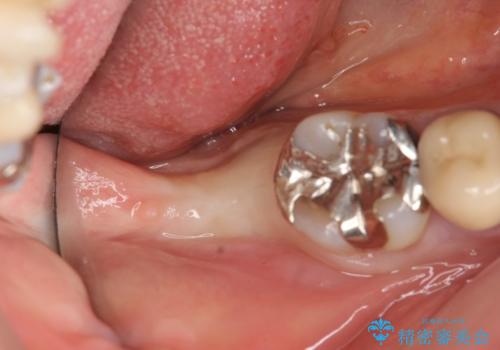

CT撮影を行い状態を確認後、インプラント(ストローマン)の埋入(一次手術)を行いました。

インプラントと骨の定着を待った後に二次手術を行い、カスタムアバットメント、オールセラミッククラウンによる補綴を行いました。

カスタムアバットメントは患者様それぞれの歯茎に合わせて製作されたオーダーメイドのアバットメントです。

既製のアバットメントに比べ適合がよく、高い清掃性を誇ります。